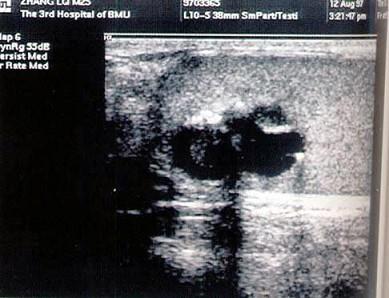

问题 患者男,21岁,发现睾丸无痛肿块,局部不规则,结合超声图像,最可能的诊断是?(?)

选项 A.精原细胞瘤 B.睾丸畸胎瘤 C.精母细胞瘤 D.睾丸腺癌 E.睾丸囊肿

答案 B